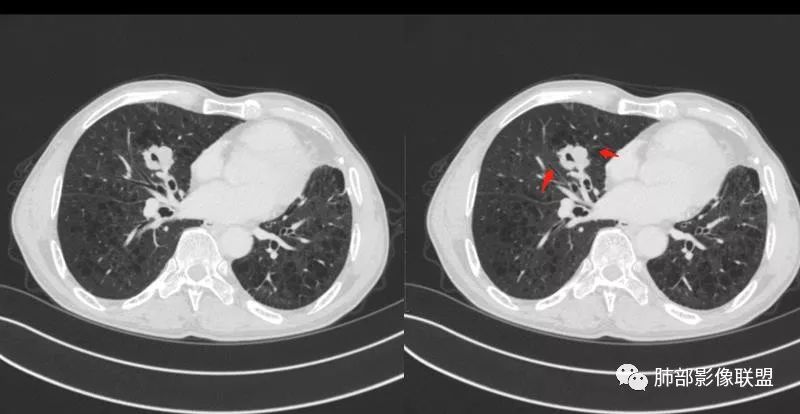

患者老年男性,间断咳嗽、咳痰伴痰中带血2个半月就诊,胸CT:右肺中叶内侧段占位性病变,病变可见分叶,周围可见结节影。病灶内可见厚壁空洞,洞壁光滑,未见洞壁结节,右肺中叶内侧段近肺门处支气管壁增厚。诊断:考虑结核,鉴别:肺癌,建议痰找抗酸杆菌、支气管镜检查 医学百科网 | YxBaike.Com

老年人,右肺中叶內侧段结节病灶,内见不规则空洞,近端可见引流支气管,其支气管壁增厚。结节病灶周围可见卫星灶,考虑肉芽肿病变,结核可能。 医学百科网 | YxBaike.Com

老年男性,肺气肿背景,右肺中叶结节,边缘膨隆,有分叶及细毛刺,厚壁空洞,考虑恶性,腺癌。 医学百科网 | YxBaike.Com

老年男性,咳嗽痰血,影像:肺气肿背景,右肺中叶结节,分叶膨隆为主,部分平直,空洞,内壁光滑,壁厚,未见索条?树芽征、引流支气管,考虑恶性,男性、肺气肿、小病灶空洞鳞癌可能性大,需要与TB鉴别。 医学百科网 | YxBaike.Com

右肺中叶内侧段实性病灶,病变可见深分叶,棘突,毛刺,周围多发结节影。病灶内可见厚壁空洞,内壁光滑,未见壁结节,增强轻度强化,右中叶内侧段支气管壁增厚。诊断:肉芽肿性病变,结核?隐球?鉴别:肺癌

晨读,老年男性,肺气肿背景,右肺中叶结节,边缘膨隆可见分叶,边缘毛糙,内可见小空洞,强化后呈轻度强化,可见血管影,首先考虑肺癌,建议支气管镜检查,除外结核。 医学百科网 | YxBaike.Com

晨读,有个问题,左肺体积减小?纵隔左移,右肺代偿?左肺有没有手术史?假如是癌手术,要考虑转移的问题。影像,右肺中叶不规则分叶结节,支气管开口通畅,门口到肿块中间堵塞,到肿块近边缘又能看见走形,有毛刺,内沙砾样钙化,强化给的是延迟期,轻度强化或无强化,考虑恶性。需要鉴别结核。 医学百科网 | YxBaike.Com

晨读:几个征象的认定,1.是空洞还是空腔?未见明确与支气管相通,空洞/空腔形态不规则,内部光滑;2. 有血管穿行?见血管影穿过无明显破坏;3.有没有强化?没给出平扫,猜测有轻度强化、较均匀;3.分叶、毛刺均有;总体判断:MT可能大,其内为空腔而非空洞、加之有血管穿行,考虑为生长速度快包绕所致,不首先考虑鳞癌,以小细胞癌或腺癌可能。 医学百科网 | YxBaike.Com

晨读病例:患者老年男性,间断咳嗽、咳痰伴痰中带血2月余。实验室检查无明显异常升高。胸部CT:肺气肿背景,右肺中叶内侧段占位,密度不均,见分叶,边缘膨隆,部分可见边缘平直,支气管部分变窄、部分扩张,增强轻度强化,内可见低密度灶。综合考虑良性病变可能大,结核首先考虑,鳞癌待排。 医学百科网 | YxBaike.Com

老年男性,肺气肿背景,间断咳嗽、咳痰伴痰中带血2个半月,右肺中叶结节,边缘部分膨隆,部分平直,有小结节堆积感,中间空洞不规则,近端引流支气管扩张,壁增厚,这样的改变有三个可能,腺癌,鳞癌,结核,但小于3cm的腺癌一般不形成坏死空洞,更不会与支气管相通出现咳痰咳血症状,鳞癌小于3cm未经治疗也一般不与支气管相通,除非囊腔型鳞癌,但这个周围不是硬壳样改变。所以考虑结核可能。

晨读病例:老年男性,咳嗽痰中带血俩月,肺气肿背景,右肺中叶不规则结节影,有分叶,内有空洞还是扩张支气管?不均匀轻度强化,内有血管进入。考虑恶性肿瘤,鳞癌?

晨读:患者男性,68岁,间断咳嗽,咳痰伴痰中带血2个月。CEA轻度升高。肺气肿背景。左侧胸廓塌陷欠对称,右肺中叶结节,边缘膨隆有浅分叶,支气管未见明确鼠尾样截断,结节內似有点状偏高密度影,结节内是小空洞?还是扩张的支气管?结节周围未见卫星灶。叶间裂无牵拉,收缩不明显。腺癌放后吧,在鳞癌和结核之间鉴别,肯定建议支气管镜检查。考虑恶性,猜个鳞癌。

良恶性征象都有,恶性征象多于良性,空洞呈偏心,壁厚薄不均,首选恶性,TB放后。 医学百科网 | YxBaike.Com

老年男性,咳嗽痰血,肺气肿,右肺中叶结节,分叶膨隆为主,部分平直,空洞,内壁光滑,壁厚,轻度强化,考虑恶性,鳞癌?与TB鉴别。

尘缘:今天这个有点不好定,良恶性征像都有。感染依据,临床症状,近端引流支气管扩张,壁增厚,结节有小结节堆积感,边缘部分平直。 医学百科网 | YxBaike.Com

初学者:1.边缘彭隆,分叶,结节状堆积,比较符合恶性,尤其腺癌。2.支气管远端扩张,这一点会让人想起结核,但是形态不好,我还是结核放第二吧。3.淋巴瘤虽然支气管扩张,但是一般扩张比较均匀,不符合。鳞癌支气管应该堵塞不符合。小细胞也不会有支气管,不符合。隐球菌支气管堵塞的,不符合。这个支气管还是通畅,内部还不是太紧密,破坏也少,那腺癌和结核肉芽肿鉴别,再放一个转移。左肺确实好像隐瞒了什么,说不定也是癌术后。

南边:

定位中叶,左上胸廓狭窄,需要相关的病史

肺气肿明显 医学百科网 | YxBaike.Com

中叶内侧段结节 医学百科网 | YxBaike.Com

少许细小结节

我们的主要目标:中叶内侧段结节 医学百科网 | YxBaike.Com

深分叶,部分边缘膨隆,也有部分平直 医学百科网 | YxBaike.Com

边缘光滑

部分边缘有短毛刺

我需要看这个是不是近端支气管堵塞,如果近端支气管明确,我就高度怀疑癌 医学百科网 | YxBaike.Com

空泡征 医学百科网 | YxBaike.Com